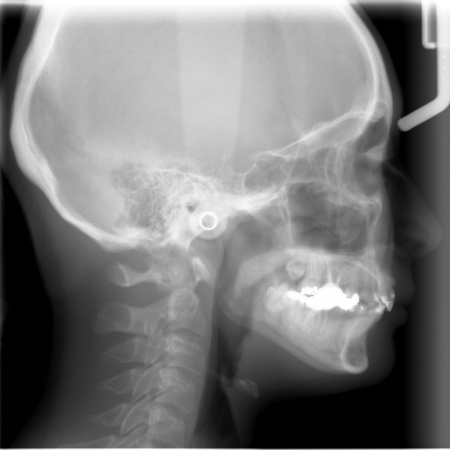

| カウンセリング | 拝見したところ、上前歯が大きく前に出ている上顎前突であり、上下の前歯が噛み合わずに口を閉じても前歯同士が接触しない「開咬(かいこう)」の状態でした。 レントゲン撮影をして詳しく調べた結果、歯の位置だけでなく、骨格的な問題があることが分かりました。 また、前歯で食べ物をうまく噛み切ることができないため、奥歯にも強い負担がかかっているだけでなく、このまま放置すると、奥歯がすり減ったり痛みが生じたりするリスクもあります。 以上のことから、噛み合わせを改善する治療が必要だと診断しました。 |

患者様の場合、骨格的な上顎前突が噛み合わせを乱している主な原因であることから、矯正治療では前歯を後方へ大きく動かすためのスペースを確保する必要があります。 そのため、今回は以下2つの方法を提案しました。 ①抜歯後、アンカースクリューを用いたワイヤー矯正 メリット:骨格的な上顎前突に対応しやすく、前歯を大きく後方へ動かすことができる ②取り外し可能な装置を使用するマウスピース矯正 メリット:装置が透明で目立ちにくく、取り外しができる 以上のメリットとデメリットを丁寧にお伝えしたところ、患者様は①のアンカースクリューを用いたワイヤー矯正を選択されました。 まず、上顎の左右奥歯を抜き、前歯を後方に動かすためのスペースを確保します。 治療の結果、前歯が正しく噛み合うようになり、横顔のバランスも整いました。 矯正治療終了後は、歯が元の場所に戻らないよう上下前歯に保定装置(リテーナー)を装着し、治療を終了しています。 |